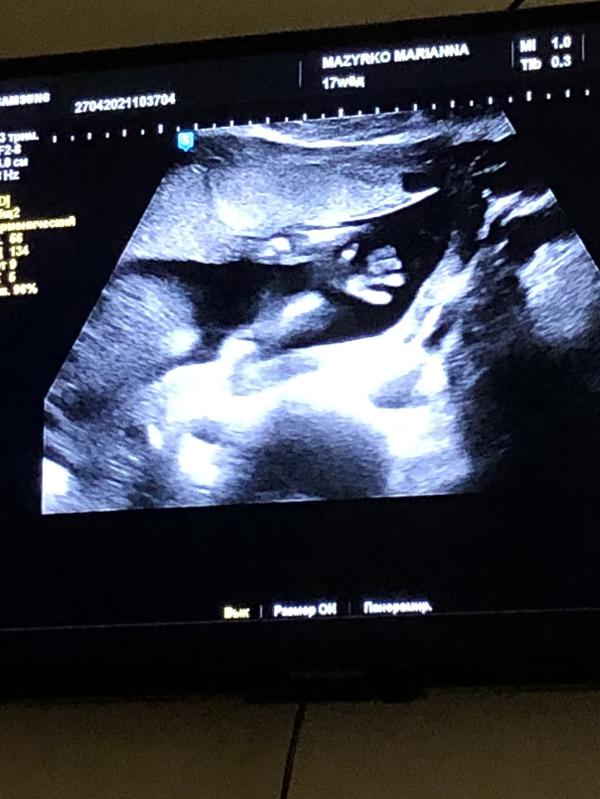

p.s. На третьем фото у нашего парня все 👌🏻))))